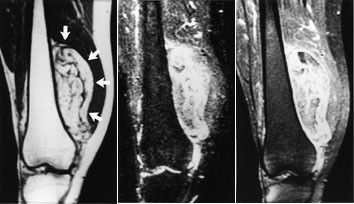

Ved osteogent sarkom og Ewings sarkom kan MR med snittplan i knokkelens lengdeakse nøyaktig fastslå øvre og nedre grense for tumorutbredelse i beinmargen (fig 5), påvise metastaser innenfor samme margrom og innvekst i ledd. Dette er forhold som har stor betydning for omfanget av kirurgiske inngrep. Som regel har tumor på diagnosetidspunktet brutt gjennom knokkelen og gitt opphav til en ekstraossøs komponent. Med snittplan perpendikulært på knokkelen kan MR vise om tumor affiserer kar og nerver, og hvilke muskler den ligger an mot eller infiltrerer. MR kan styre biopsitakingen til de områder av tumor hvor det er størst sannsynlighet for å finne representativt vev.

Konvensjonelle røntgenbilder er første trinn i utredningen av mistenkte bløtvevssvulster (12). De viser underliggende skjelettdeformitet, beinaffeksjon og bløtvevsforkalkninger. Forkalkninger kan ikke påvises med MR. MR er allikevel den beste metoden, fordi den i tillegg til å vise de anatomiske forhold også fremstiller væske, nekrose, blødning, fett og annet bløtvev (fig 6 – 8). Basert på vekstmønster og signalforhold kan vevsspesifikk diagnose stilles i 20 – 40 % av tilfellene. Det er oftest ikke mulig å angi om en bløtvevstumor er benign eller malign. Nekrose er den enkeltfaktor som sterkest peker i retning av malignitet. Andre faresignaler er stor tumor, uskarp avgrensning med omgivende ødem, heterogent signal og beinaffeksjon. Men høymaligne bløtvevssvulster kan være velavgrenset med en pseudokapsel.